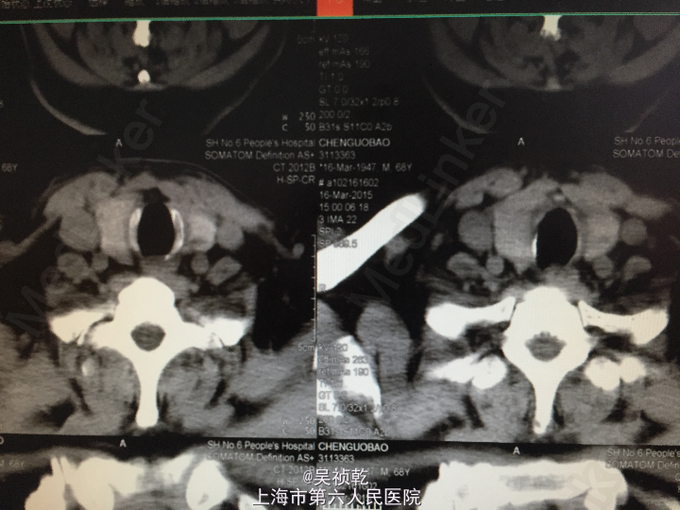

查体:颈软,气管居中,无颈静脉怒张,双侧甲状腺轻度肿大。右侧可触及多个结节,质硬,活动度低,直径大小1.0-1.5cm不等。 辅查:2015-3-14 门诊化验检验报告:白细胞 4.7 *10^9/L ,红细胞 5.13 X10^12/L ,血红蛋白 160 g/L ,细胞比积 48.9 % ,血小板 169 X10^9/L ,淋巴细胞百分比 31.7 % ,中性细胞百分比 55.8 % 。门诊化验检验报告:凝血酶原时间 10.7 秒 ↓,国际标准化比率 0.97 ,部分凝血活酶时间 21.9 秒 。生化检验报告:血糖 5.47 mmol/L 。生化检验报告:总蛋白 71 g/L ,白蛋白 47 g/L ,谷丙转氨酶 25 U/L ,谷草转氨酶 17 U/L ,线粒体谷草转氨酶 8 U/L ,碱性磷酸酶 44 U/L ,γ-谷氨酰酶 24 U/L ,总胆红素 15.4 μmol/L ,直接胆红素 5.7 μmol/L ,尿素 6.7 mmol/L ↑,肌酐 89 μmol/L ,钙 2.36 mmol/L 。 放免DPC(同位素)检验报告:游离T3 5.24 pmol/L ,游离T4 20.09 pmol/L ,促甲状腺激素 3.14 mIU/l ,抗甲状腺球蛋白抗体 16.75 KIU/L ,抗甲状腺过氧化物酶抗体 8.90 KIU/L 。 2015-3-13 CT报告:1.两侧甲状腺多发结节,请结合临床相关检查。2.左侧梨状窝变浅,请结合临床及必要时喉镜检查。3.附见:右上颌窦囊肿可能。 2015-3-16 彩超检查报告:颈部肿块及周围淋巴结 双侧颈血管旁未见明显肿块及形态饱满淋巴结。双侧颈血管旁未见明显肿块及形态饱满淋巴结。 彩超检查报告:1.甲状腺右侧叶中部及左侧叶下极极低回声结节,符合占位性病变(Ca)。2.左侧颈部多发增大淋巴结,考虑转移性。

患者术前诊断为:双侧甲状腺乳头状癌. 患者于2015-3-18全麻下行双侧甲状腺全切除术+喉返神经探查+颈部淋巴结清扫术,先切除右侧甲状腺立即送冰冻,冰冻回报示"右侧甲状腺乳头状癌"。进一步处理右侧中央区淋巴结,切除后送病理.同法处理左侧甲状腺,左侧甲状腺次全切除后组织送冰冻,冰冻回报示"左侧甲状腺乳头状癌"。故将左侧残余甲状腺组织及中央区淋巴结一并切除.手术经过顺利,术中出血少,术中病人血压平稳,麻醉效果满意,病人安返病房。 术后病理: 右侧甲状腺 (右甲):甲状腺乳头状癌(大小0.9*0.8*0.8cm)。肿瘤组织免疫酶标记结果:CK19(+)、TPO(-)、G3(+)、MC(+)。左侧甲状腺 (左甲)甲状腺乳头状癌(大小1.2*1.0*0.7cm)。肿瘤组织免疫酶标记结果:CK19(+)、TPO(-)、G3(+)、MC(弱+)。 术后予止血、补钙、营养支持等对症治疗,术后无恶心呕吐,发音好,呼吸无困难,无口周麻木和手抽搐症状,患者病情好转出院。